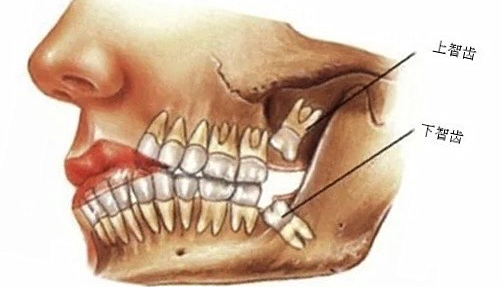

在我们的口腔中有一颗特殊的牙齿——第三磨牙,它通常在16~25岁的年龄段萌出,这是一个人心智发育逐渐成熟的时期,故第三磨牙又被称为“智齿”。然而对大多数人来说,长智齿是一段令人饱受折磨的“血泪史”:智齿萌出经常伴随着疼痛,让人寝食难安,最严重者甚至会引起全身性感染危及生命。

(智齿的解剖位置)

这还得从智齿特殊的位置和萌出时间说起。如上所述,智齿萌出年龄为16~25岁,此时人的颌骨发育已定型,基本不再变化,位于牙列最末端的智齿“姗姗来迟”,往往没有足够的萌出空间而呈阻生牙的状态,阻生智齿牙冠和周围牙龈之间形成一个“盲袋”,是食物残渣滞留,菌斑大量堆积的部位,容易引起炎症,称为“冠周炎”,是临床上最常见的智齿相关并发症,严重的急性冠周炎会引起颌骨骨髓炎、颌面部间隙感染合并全身并发症。